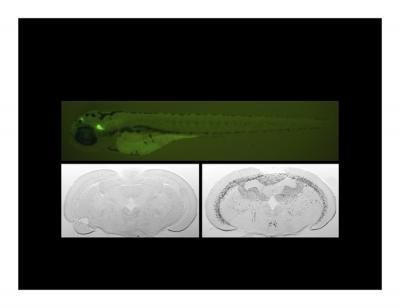

Upper panel shows fluorescently labeled neural projections in a larval zebrafish from the habenular nuclei in the forebrain to the interpeduncular nucleus in the midbrain, a pathway known to be involved in nicotine addiction.

The lower panels demonstrate neural activity (black cells) in cross sections of brains following exposure of adult zebrafish to control water (left) or to water containing nicotine (right).

Images are courtesy of Courtney Akitake and Elim Hong.